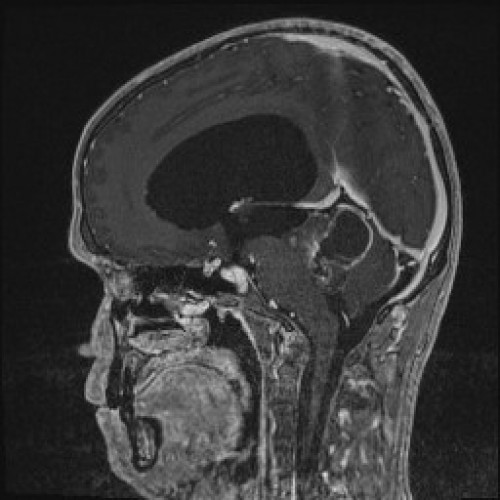

Müdigkeit und schlechte Noten

Fall-ID: 592

ICD: C75.3

ICD: G91.9

12-jähriger Junge. Die Eltern werden zu einem Gespräch bei der Klassenlehrerin gebeten, weil ihr Sohn sehr unaufmerksam geworden sei und seine Leistungen in der Schule bedenklich abgenommen hätten. Er droht das Klassenziel der 6. Klasse nicht zu erreichen.

Den Eltern war seit längerer Zeit bereits aufgefallen, dass sich ihr Sohn nach der Schule am liebsten ins Bett lege, um für eine Stunde einen Mittagsschlaf zu halten.